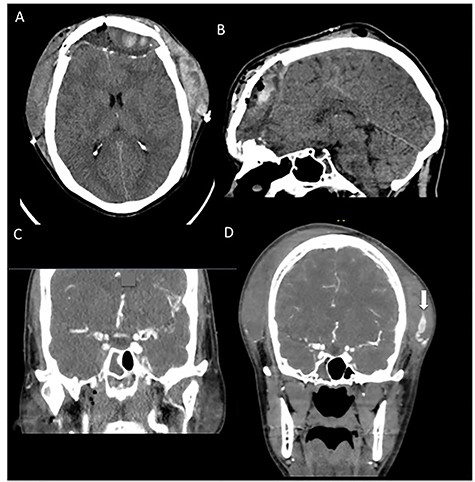

On postoperative Day 14, the patient presented to the emergency department with sudden onset of a severe headache and significant facial swelling. Imaging showed large bifrontal subdural hematoma with an associated large subgaleal hematoma (Fig. 2A, B). Computed tomography (CT) angiography was performed due to concern for vascular cause secondary to sudden onset in the setting of recent trauma and showed a 6 mm × 18 mm left STA PA (Fig. 2D) that was presumed to have ruptured due the degree of his extracranial and intracranial hemorrhage. He was taken back emergently for revision craniotomy to evacuate the subgaleal and subdural hematoma. The aneurysm was ligated intraoperatively. He tolerated the procedure well and was ultimately discharged with no outward complication at follow-up. Repeat CT angiography did not show any persistent PA.

CT angiography taken at 2 weeks postoperatively when patient returned with sudden onset of facial swelling and significant headache. (A, B) Noncontrasted CT of the head showing significant subgaleal hematoma and adjacent bifrontal subdural hematoma with associated mass effect. (C) Prior trauma imaging (CT angiography of the neck) from initial hospitalization showing no evidence of STA pseudoaneurysm. (D) CT angiography showing a large (18 mm × 7 mm) left STA pseudoaneurysm (white arrow).